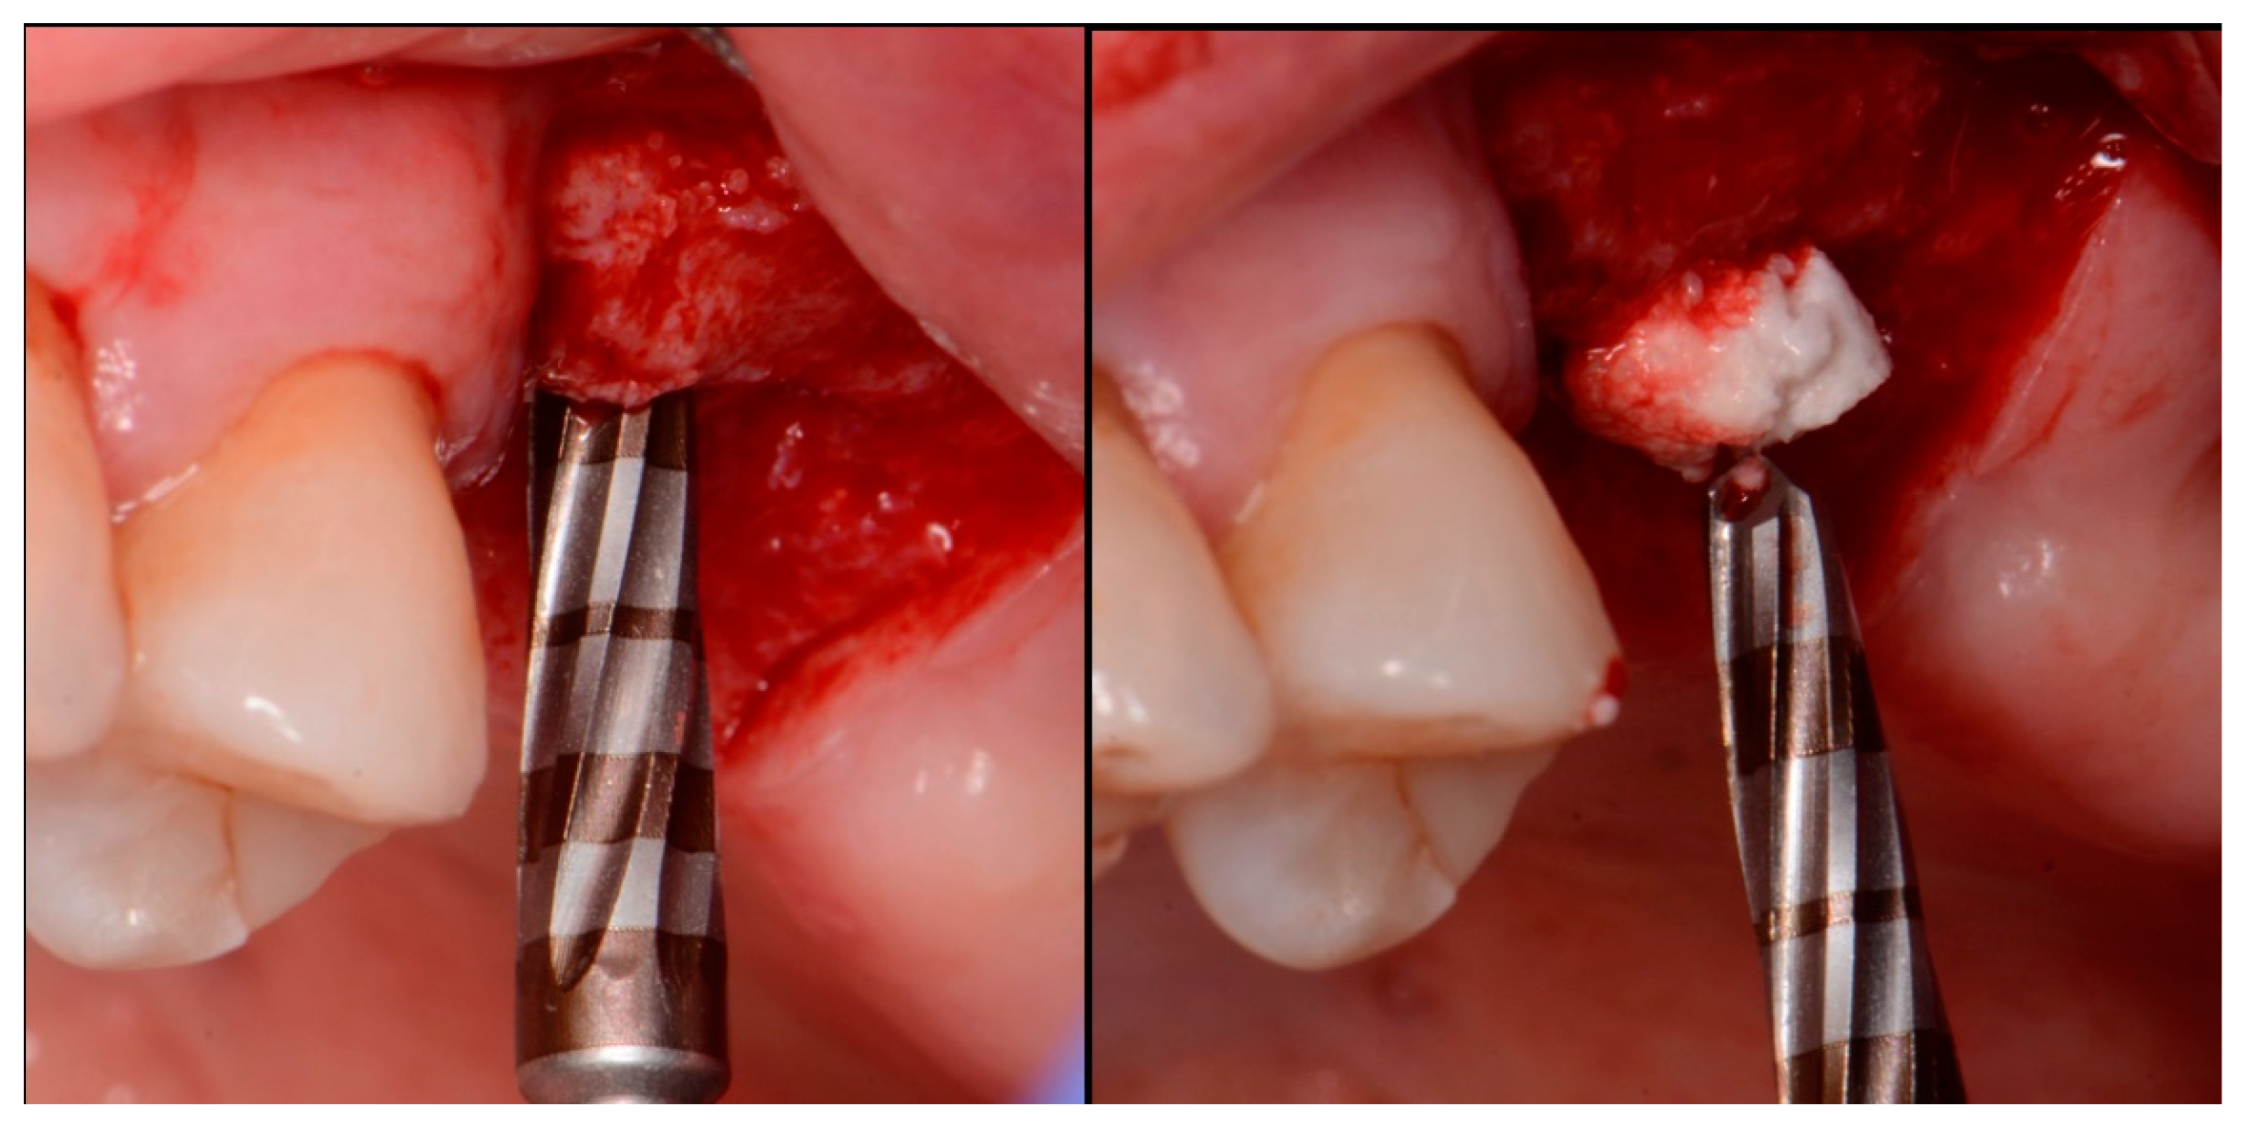

The patient returned at 10 weeks post-surgery and a periapical radiograph was obtained to evaluate the graft healing (Figure 1, right). The graft was noted to have blended with the surrounding host bone and was deemed ready for implant placement. The soft tissue covering the grafted portion of the ridge was keratinized and no inflammation was noted (Figure 2). Local anesthetic was again administered in a similar manner as the previous surgery. A crestal incision was made from the distal of the distal papilla at the 2nd premolar to a point where the 1st molar would be positioned. A releasing incision was made at the distal of the papilla and also at the posterior extent of the crestal incision and extended into the buccal vestibule. A full-thickness flap was elevated to expose the crestal ridge (Figure 3). The graft had converted to bone at the extraction sockets. A pilot drill was utilized to start the osteotomy to a depth of 4 mm, 2 mm shy of the sinus floor as measured on the radiograph. The osteotomy was increased laterally utilizing Densah osseodensification burs (Versah, Jackson, MI, USA) to a width of 4 mm (Figure 4, left). EthOss graft material that had been hydrated in the syringe was dispensed into the osteotomy and the final Densah bur was utilized to elevate the sinus floor and laterally spread the graft material to gain height for the implant placement (Figure 4, right). A 5 mm × 8 mm Paltop Addvanced (Paltop, Cesarea, Israel) implant was introduced into the site to the desired crestal depth (Figure 5, left). A cover screw was placed, and additional EthOss graft material was placed at the crest to fill a depression on the distal aspect adjacent to the implant (Figure 5, middle). A periapical radiograph was obtained to document the implant and associated sinus/crestal grafting performed at this stage (Figure 5, right).

Figure 4.

Osteotomy preparation short of the sinus floor in preparation for a crestal sinus augmentation (left) and utilization of the osteotomy drill to force EthOss graft material to elevation of the sinus area (right).